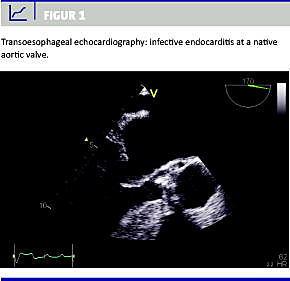

Infektiøs endocarditis (IE) er en alvorlig sygdom, der har haft en uændret høj mortalitet og morbiditet gennem de seneste tre årtier, selv om der gives relevant behandling som foreskrevet i National Behandlingsvejledning, der er udgivet af Dansk Cardiologisk Selskab (DCS). Formålet med den aktuelle undersøgelse var at opgøre alle tilfælde af sikre og mulige IE, der blev behandlet på Odense Universitetshospital (OUH) i perioden 2002-2006 med særligt fokus på bakteriologi, diagnostisk delay , komplikationer og kliniske endepunkter.

Trods fremgang i ekkokardiografisk og mikrobiologisk diagnostik har det diagnostiske delay været uændret gennem de seneste tre årtier sammenlignet med et tidligere studie. Vores undersøgelses resultater viser en øget frekvens af stafylokokinfektioner med høj morbiditet og mortalitet.

IE er fortsat en alvorlig sygdom med høj morbiditet og mortalitet især for ældre patienter og patienter med hjerteklapprotese.